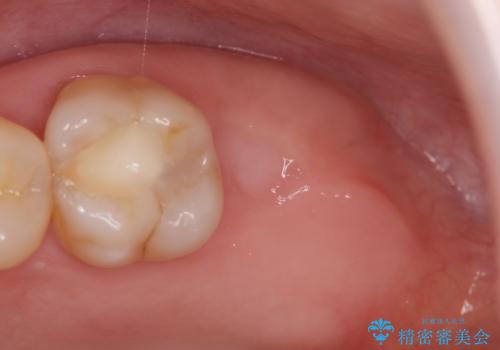

- 噛むと歯が疼いて痛い、と根管治療を希望され来院されました。

精査した結果、上顎奥歯は歯が割れてしまっており、根管治療ではなく抜歯の対象でした。

歯の抜去後、しっかりと咬合機能を回復するためインプラントを用いた治療を行っていきます。